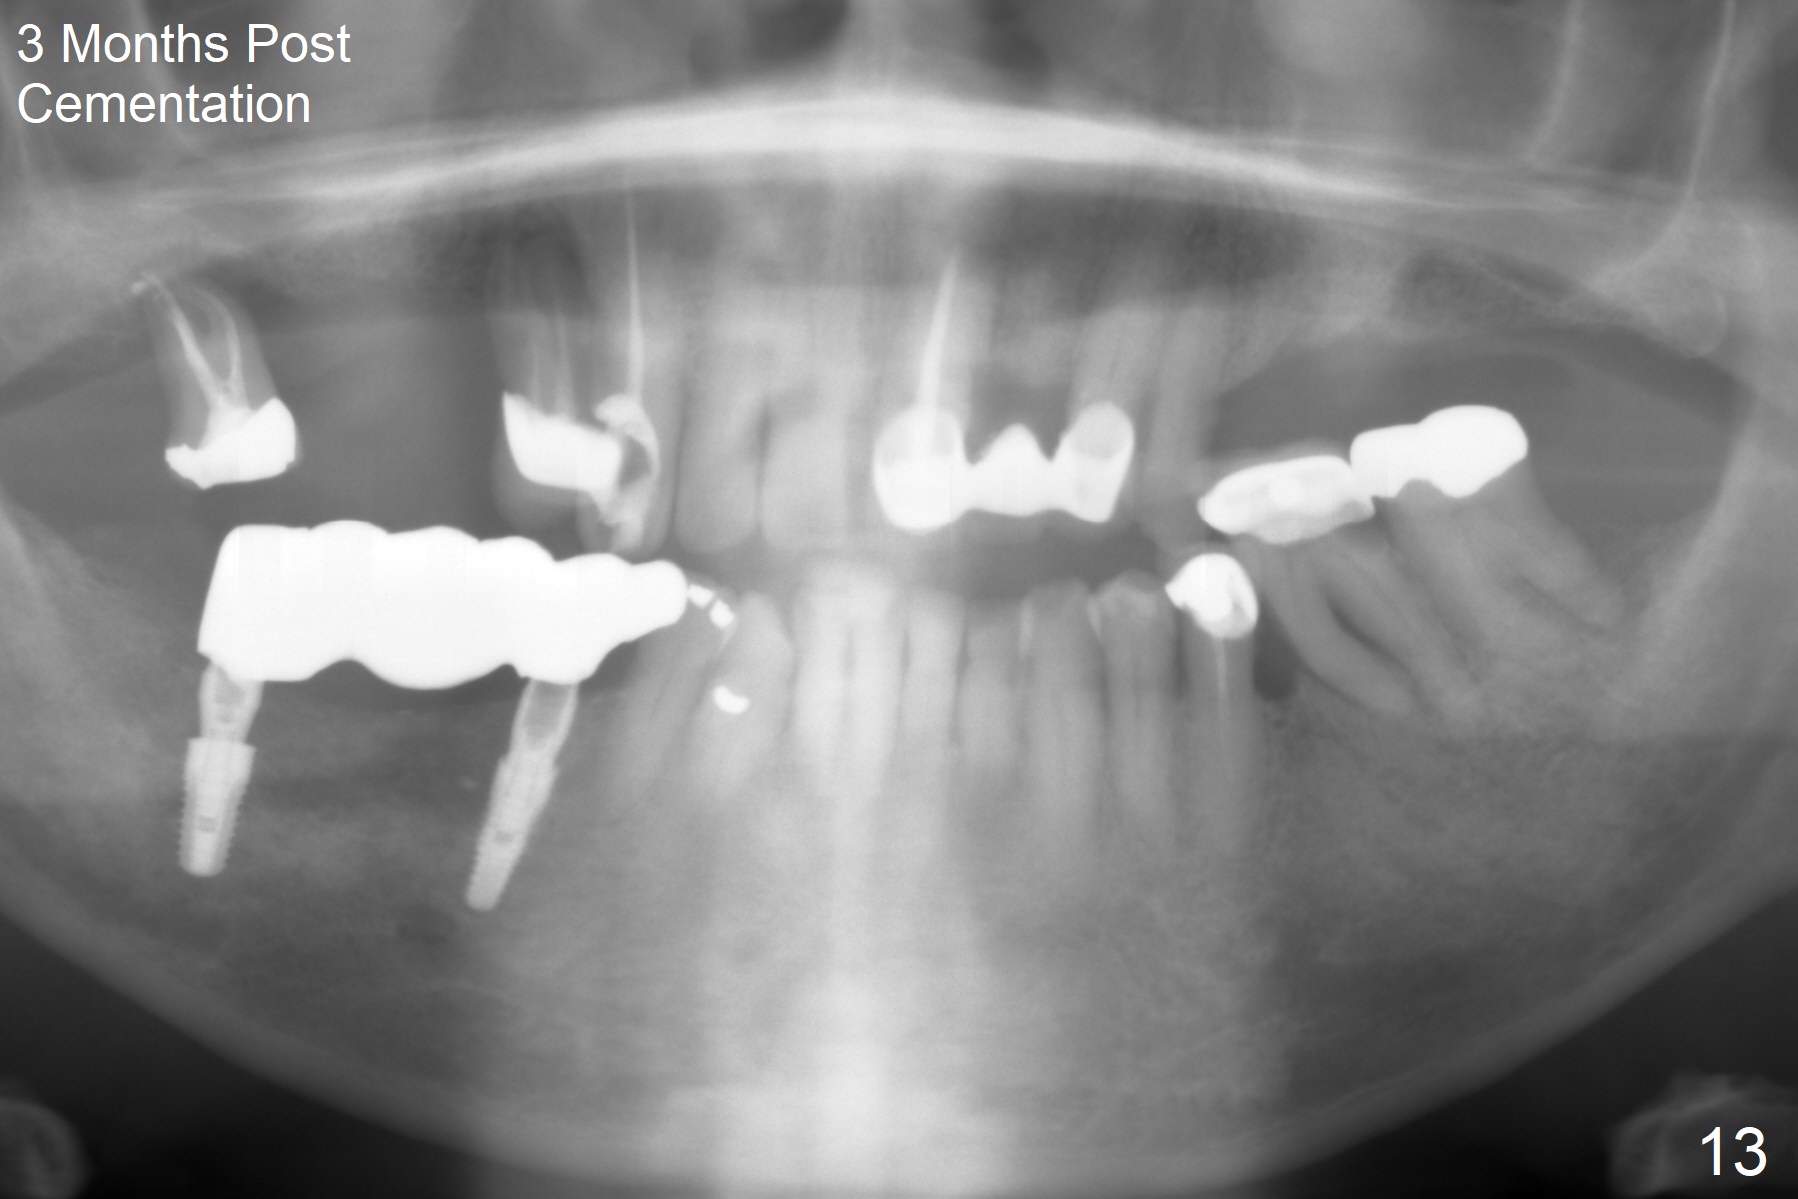

The patient will return in two weeks (total 2 months postop). The abutment at #29 will be changed to a longer one (3.9x7(6) mm). Provisional FPD will be fabricated with an emphasis to push the surrounding (especially lingual) gingiva away from the abutments, most likely using gauze as gingival retraction cord. The crown at #2 will be trimmed to have clearance. Fig.13 is taken 3 months post cementation. CBCT taken 1 year 9 months post cementation shows the uneven buccal (B) and lingual crests (Fig.14,15 arrowheads).